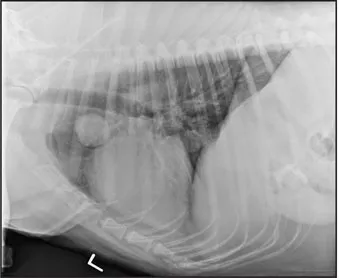

CASE 1.4 A 13-year-old spayed female mixed breed dog with a history of polyuria and polydipsia and abdominal distension. You obtain these thoracic radiographs: Fig. 1.4a, left lateral projection; Fig. 1.4b, dorsoventral projection.

1.4a